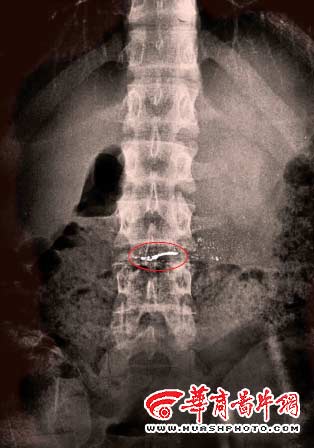

“当时大夫告诉我赶紧买牛奶,等我买牛奶回来医生已经给孩子洗胃了。”李晶说,洗完胃后医生建议到中国医科大学附属医院做进一步检查,到医大后,经过拍片、诊断确定孩子的胃中确有很多“高密度不规则异形物”,医生诊断,误食水银。

据李晶介绍,到目前为至,她已经带儿子拍了3次片,最后一次发现胃里还有少量水银,但已经比第一次发现时少了很多。